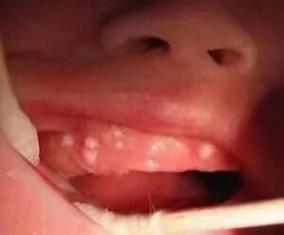

最可能的原因:鹅口疮

这是两个月宝宝口腔白点最常见的原因。

症状描述:

- 白点像奶渍或雪花,但用棉签或湿纱布擦不掉。

- 白点周围没有明显的红肿,宝宝通常不疼也不痒。

- 白点可出现在口腔的任何部位,如舌头、上颚、内颊、牙龈等,严重时可能蔓延到咽喉部。

- 有时白点会融合成大片白色的假膜。

如何初步判断: “擦不掉”是关键! 您可以尝试用消毒棉签轻轻擦拭一下白点,如果是奶渍,很容易擦掉,下面是正常的粉红色黏膜,如果是鹅口疮,会发现白点牢牢地附着在黏膜上,强行擦拭会留下红色、出血的创面,宝宝会因此哭闹。